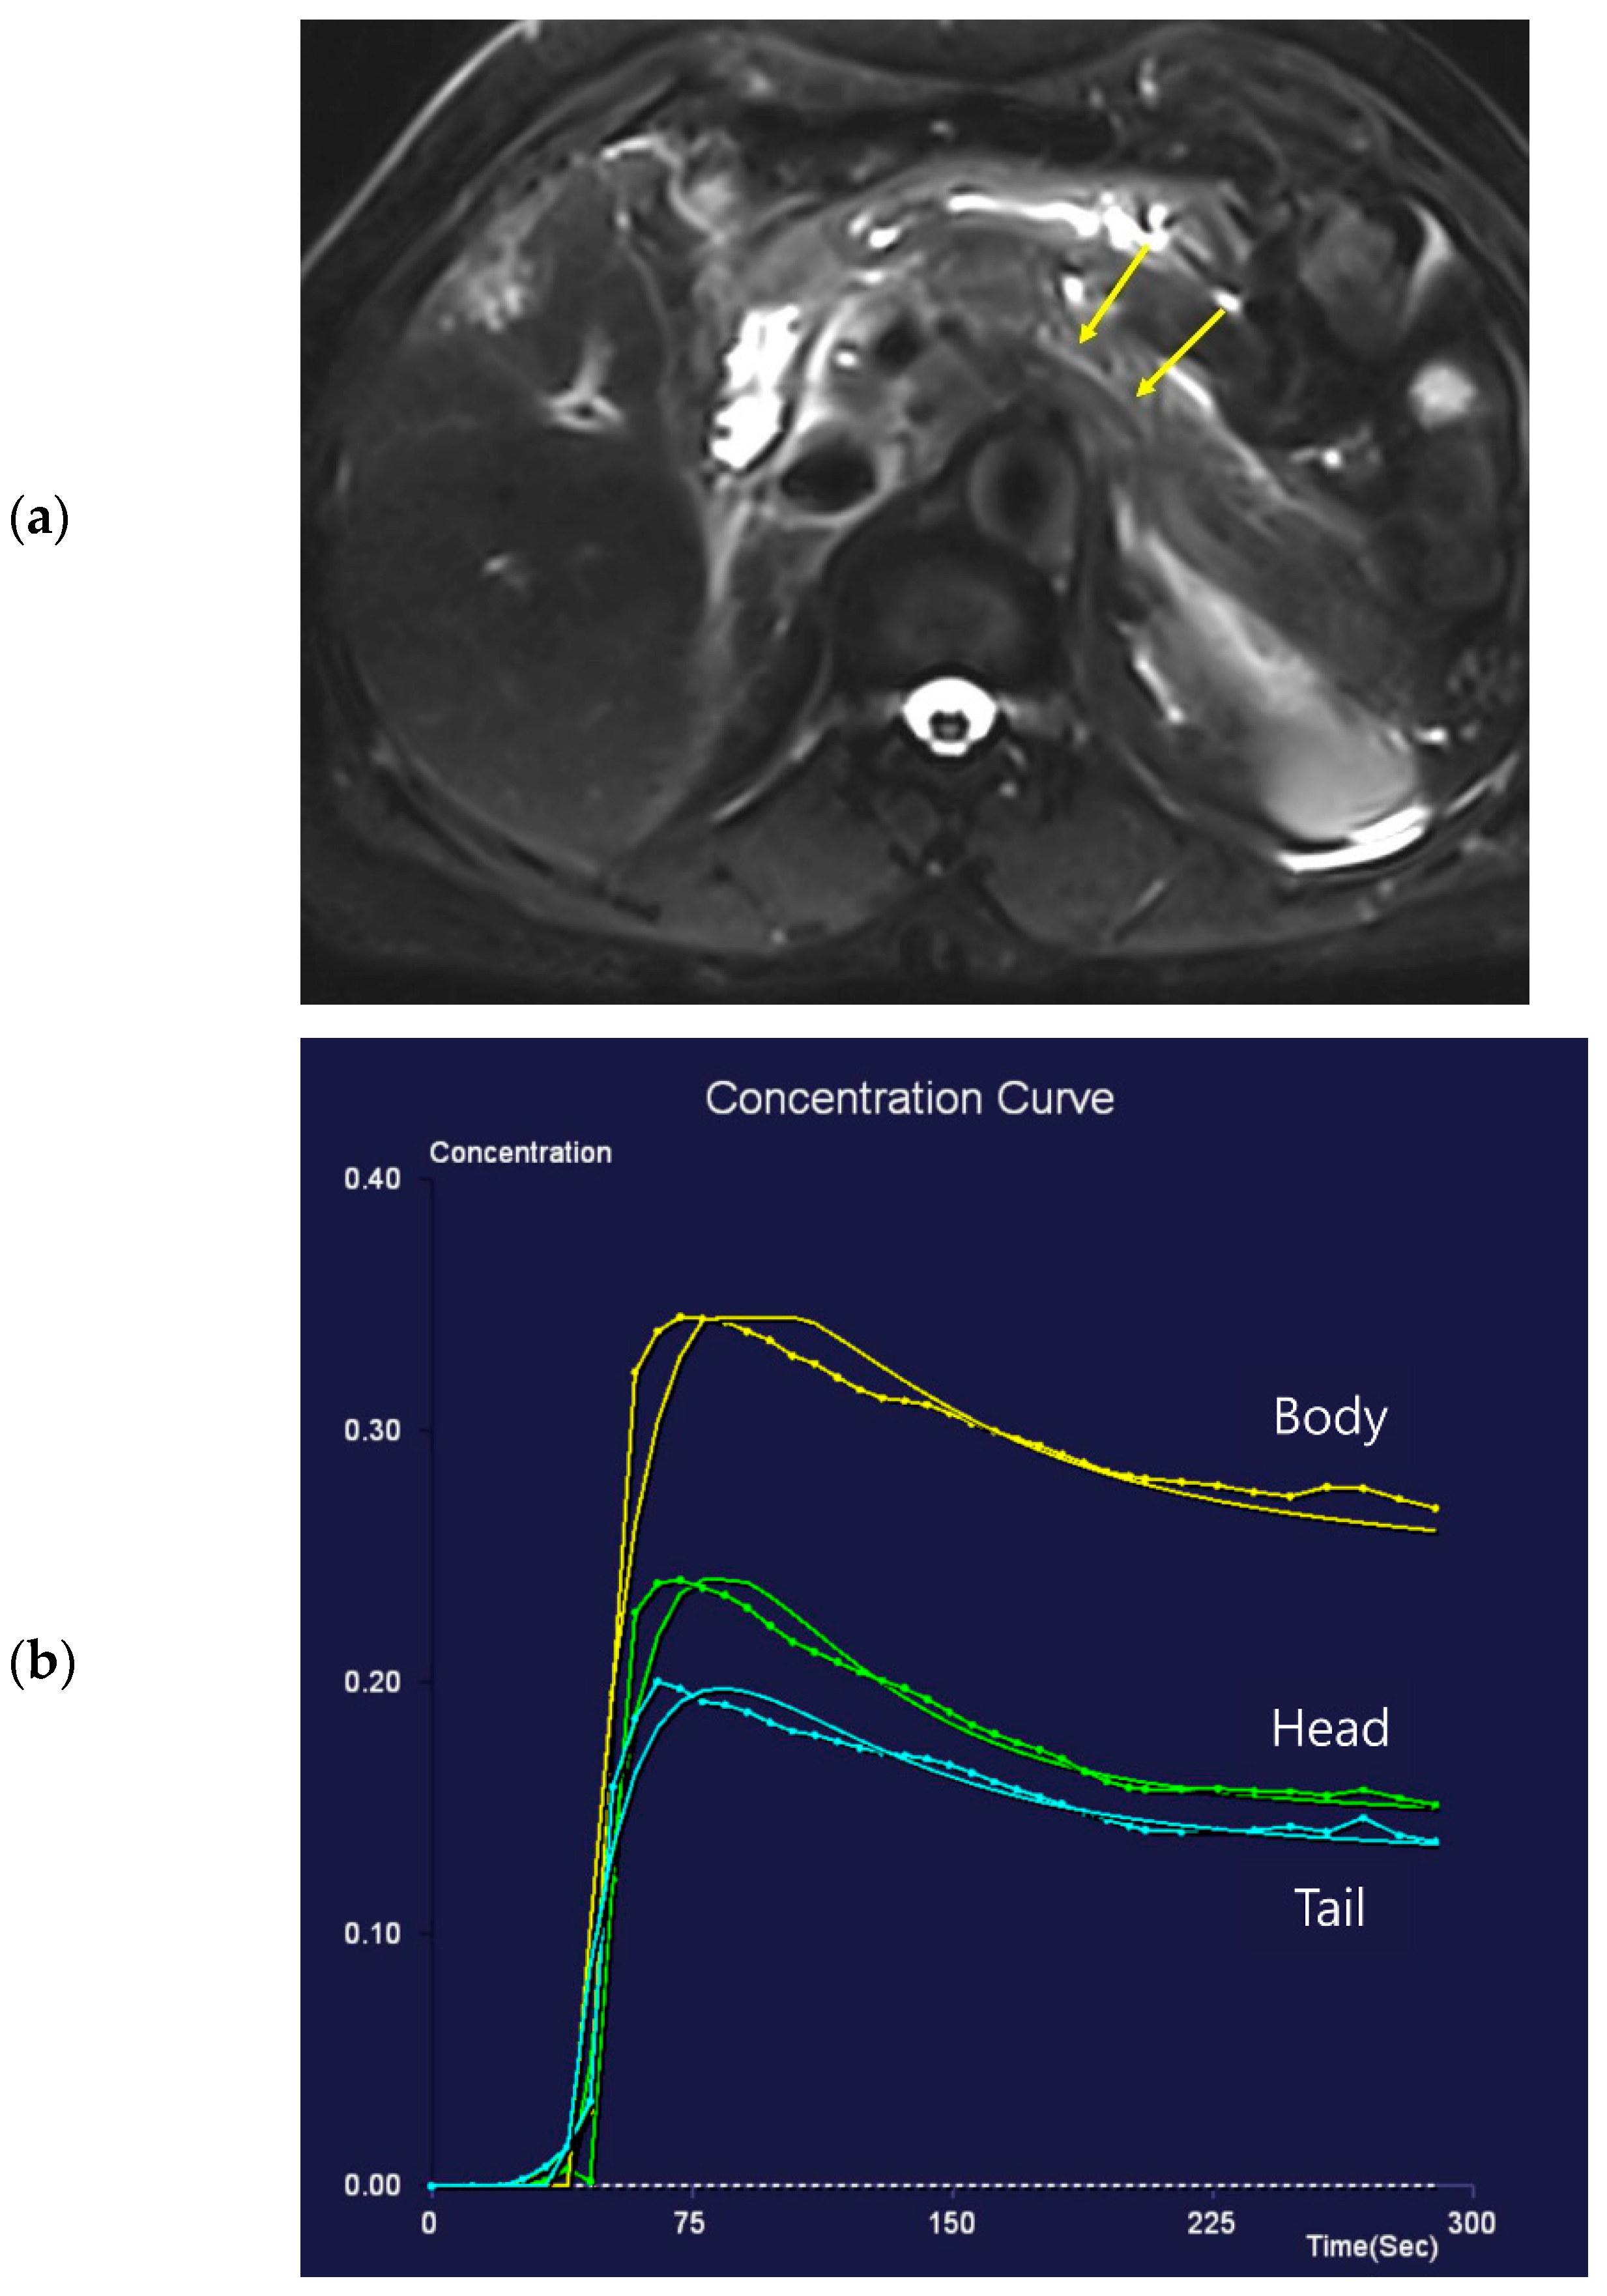

Figure 3. Eighty-nine-year-old female patient undergoing an MRI to evaluate pancreatic focal lesions. Diffuse pancreatic dilatation (arrows) is noted on T2-weighted imaging (a), and a 2.5 cm mass suspected to be pancreatic cancer is noted in the pancreatic head (not presented). Dynamic contrast-enhanced curves show gradual enhancement with stable signal intensity in the pancreas head, body, and tail (b).